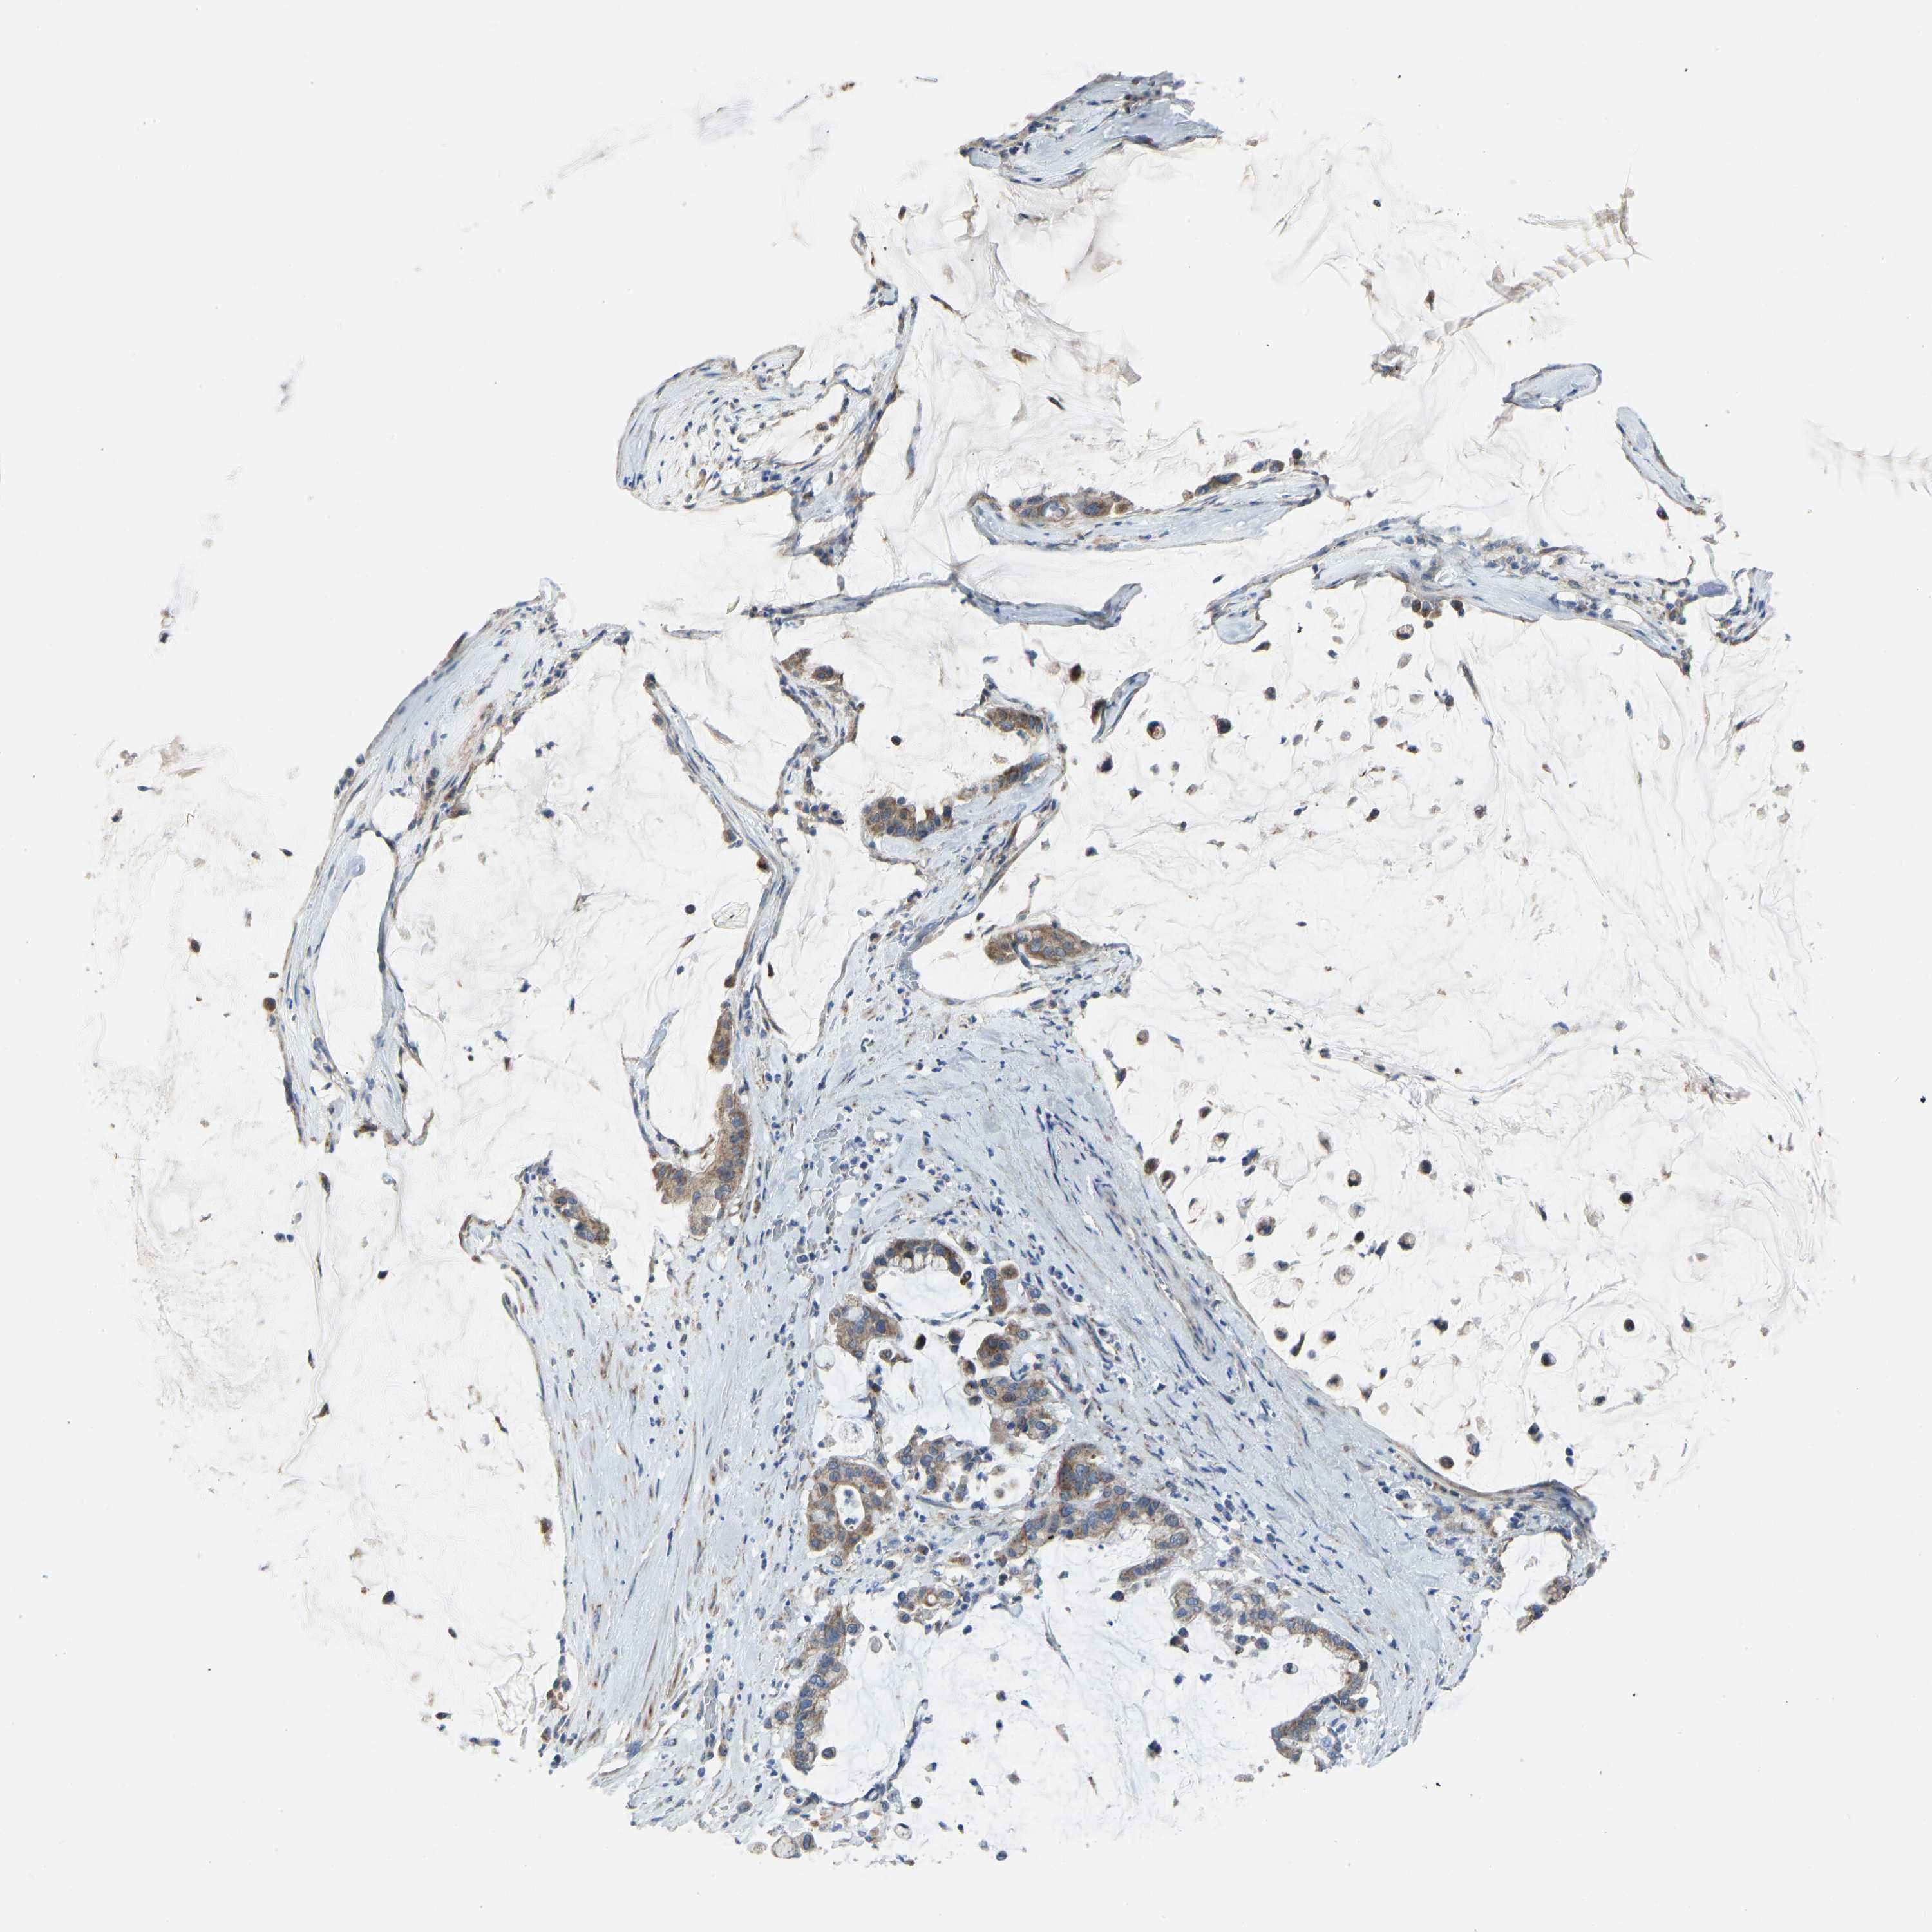

PANCREATIC CANCER - Protein expressioni

A mouse-over function shows sample information and annotation data. Click on an image to view it in a full screen mode. Samples can be filtered based on level of antibody staining by selecting one or several of the following categories: high, medium, low and not detected. The assay and annotation is described here.

Note that samples used for immunohistochemistry by the Human Protein Atlas do not correspond to samples in the TCGA dataset.

Antibody stainingi

Antibody staining in the annotated cell types in the current human tissue is reported as not detected, low, medium, or high, based on conventional immunohistochemistry profiling in selected tissues. This score is based on the combination of the staining intensity and fraction of stained cells.

Each image is clickable and will lead to virtual microscopy that enables deeper exploration of all samples and also displays staining intensity scores, fraction scores and subcellular localization as well as patient and tissue information for each sample.

Antibody HPA016552

Staining

High

Medium

Low

Not detected

Intensity

Strong

Moderate

Weak

Negative

Quantity

>75%

75%-25%

<25%

None

Location

Nuclear

Cytoplasmic/membranous

Cytoplasmic/membranous,nuclear

Adenocarcinoma, NOS